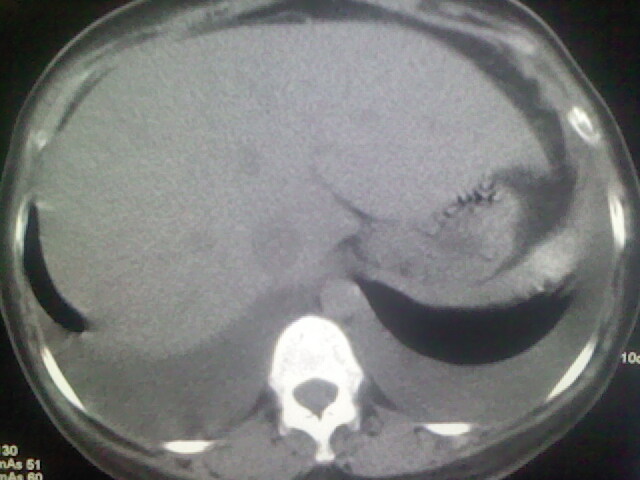

女,24,剖腹产后,突觉胸痛,干咳,不能平卧

双肺“肺泡性肺水肿” “胸腔积液”!

肝脾大,双侧胸腔积液,双肺水肿,肺动脉[包括远端小动脉],左右心房,左心室增宽,右心室主动脉无明显改变,符合左心功能不全征;;建议除外二尖瓣关闭不全,扩张性心肌病

临床资料及影象表现支持围产期扩张型心肌病改变,心衰。

考虑产后心肌病,心功能不全,肺水肿,双侧胸腔积液。不排除羊水栓塞可能。